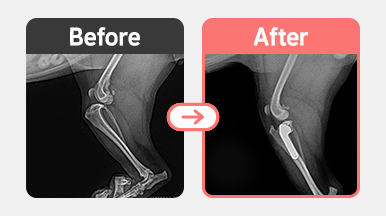

[슬개골 탈구 수술] 포메라니안 / 4살 / 양측 슬개골탈구 2기

2025-11-28